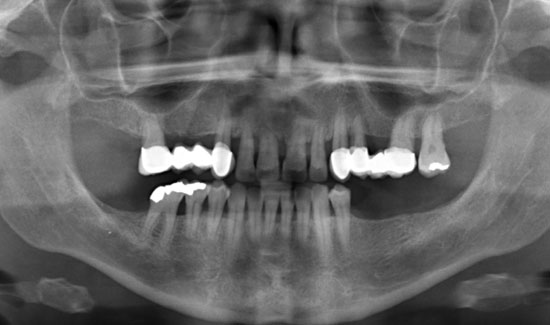

Fig. 1: Orthopantomogram